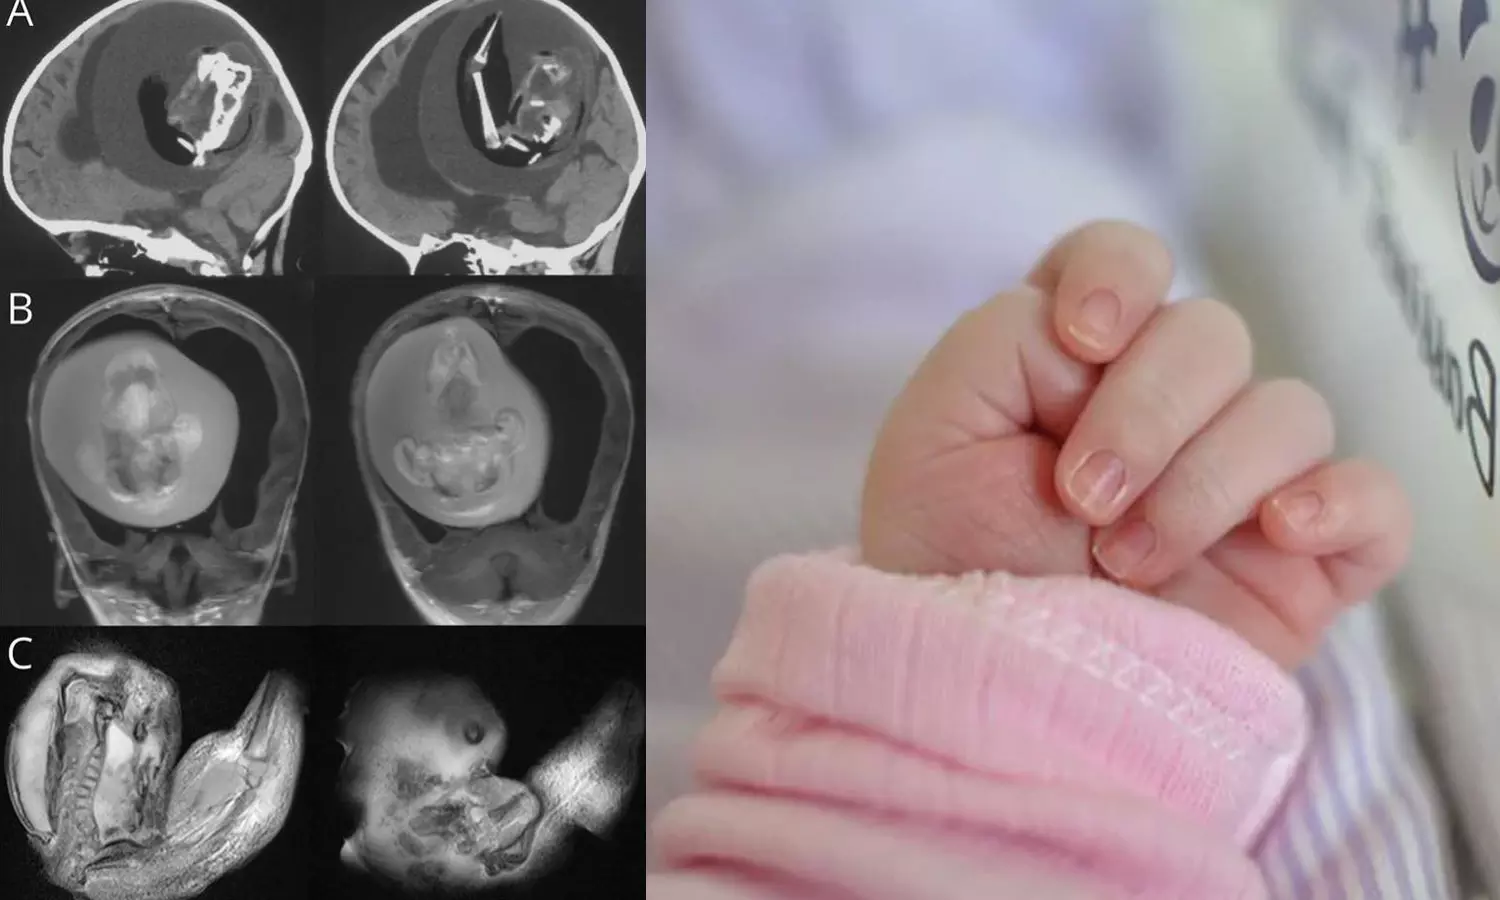

ബെയ്ജിങ്: ഒരു വയസുള്ള കുഞ്ഞിന്റെ തലച്ചോറിനുള്ളിൽ ഇരട്ടയുടെ ഭ്രൂണം. കേൾക്കുമ്പോൾ അതിശയം തോന്നുന്നുണ്ടോ?. എന്നാൽ വിശ്വസിച്ചേ പറ്റൂ. ചൈനയിലാണ് സംഭവം. ഒരു വയസ് മാത്രം പ്രായമുള്ള കുഞ്ഞിന്റെ തലച്ചോറിനുള്ളിൽ നിന്ന് ഇരട്ടയുടെ ഭ്രൂണം നീക്കം ചെയ്തതായി ഷാങ്ഹായിയിലെ ഡോക്ടർമാർ പറഞ്ഞു. ന്യൂറോളജി ജേണലിൽ പ്രസിദ്ധീകരിച്ച ഒരു പഠനത്തിലാണ് ഇക്കാര്യം വ്യക്തമാക്കുന്നത്.

തല വലുതായ കുഞ്ഞിനെ ആശുപത്രിയിൽ പ്രവേശിപ്പിച്ചപ്പോൾ നടത്തിയ സ്കാനിങ്ങിലാണ് ഞെട്ടിക്കുന്ന വിവരം അറിഞ്ഞത്. ഇരട്ടയുടെ ഭ്രൂണത്തിന് കൈകാലുകളും എല്ലുകളും വിരലുകൾ പോലെയുള്ള മുകുളങ്ങളും വികസിച്ചതായി ഡോക്ടർമാർ പറഞ്ഞു.

ഇൻട്രാവെൻട്രിക്കുലാർ ഫീറ്റസ്-ഇൻ-ഫീറ്റൂ എന്നറിയപ്പെടുന്ന ഈ അവസ്ഥ ഗർഭാശയത്തിൽ ഇരട്ടകൾ കൂടിച്ചേരുമ്പോഴാണ് സംഭവിക്കുന്നതെന്ന് ഡോക്ടർമാർ പറയുന്നു. 'എന്നാൽ ഒന്നിന്റെ വളർച്ച മാത്രമേ കൃത്യമായി നടക്കുന്നുള്ളൂ'- മിയാമി ഹെറാൾഡ് റിപ്പോർട്ട് ചെയ്തു. ഒരു കുട്ടിയുടെ വയറ്റില്‍ മറ്റൊരു ഭ്രൂണം വളരുന്ന അവസ്ഥയാണിതെങ്കിലും ചിലപ്പോഴൊക്കെ അത് തലച്ചോർ ഉൾപ്പെടെയുള്ളവയിലും ആവാം.

ഭ്രൂണത്തിന്റെ ജീനോം സീക്വൻസിങ് ഇത് ഒരു വയസുള്ള കുഞ്ഞിന്റെ ഇരട്ടയാണെന്ന് കണ്ടെത്തിയതായി പഠനം പറയുന്നു. ഇത്തരം കേസുകൾ ലോകത്ത് വളരെ അപൂർവമായി മാത്രമേ കാണപ്പെടുന്നുള്ളൂ, 10 ലക്ഷം കുട്ടികളിൽ ഒരാൾക്ക് മാത്രമേ ഇത് സംഭവിക്കൂ.